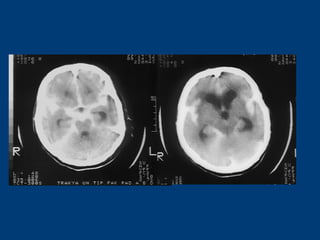

MASİF SPONTAN SAK + ICH + İVH + SDH…MASİF SPONTAN SAK + ICH + İVH + SDH…

MASİF SPONTAN SAK + ICH + İVH +…MASİF SPONTAN SAK + ICH + İVH +…

• 58 yaşında bayan hasta58 yaşında bayan hasta

• Ani bilinç kaybı şikayetiyle acilAni bilinç kaybı şikayetiyle acil

polikliniğe getirildipolikliniğe getirildi

• İlk NM:İlk NM: Bilinç kapalı; GKS: 5Bilinç kapalı; GKS: 5

Pupillalar anizokorikPupillalar anizokorik

YBÜYBÜ

5. günde exitus5. günde exitus